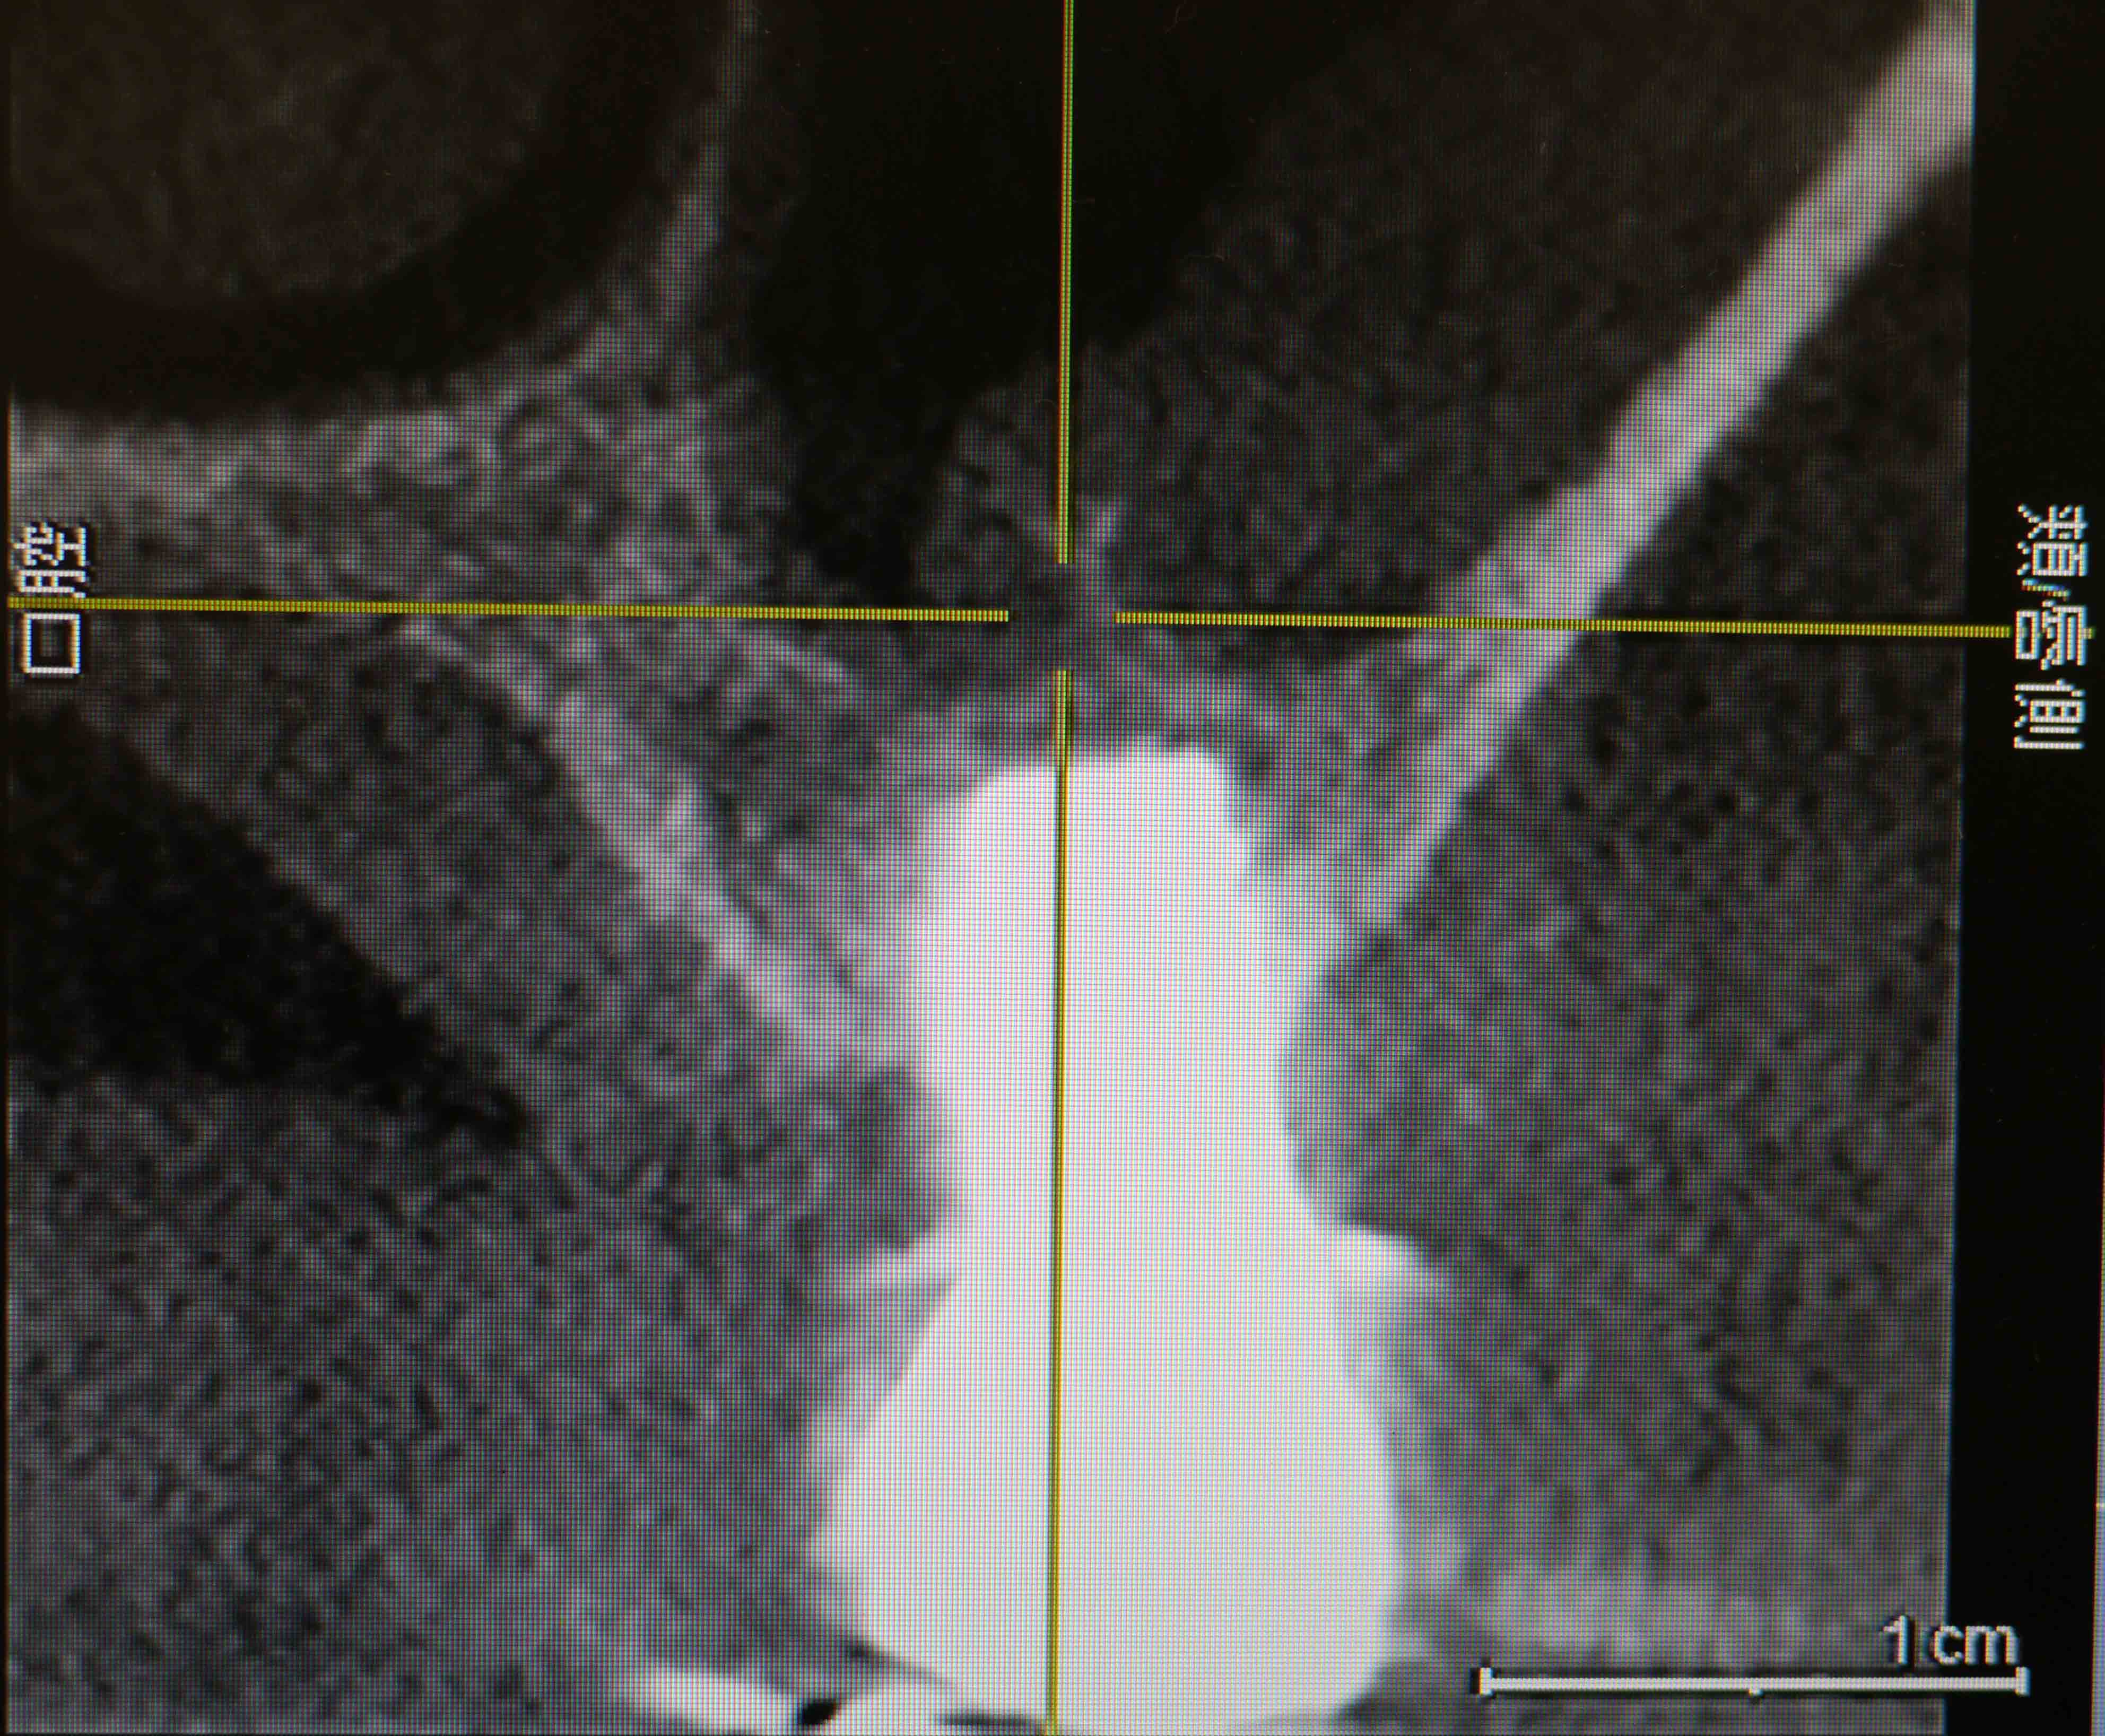

CT画像1

平成24年9月 手術前のCT画像

上顎洞底の骨の厚さが右上7番で最低4mm、6番で2mm程度

埋入予定の骨を側面(頬側)から見たCT画像